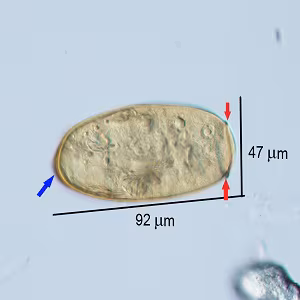

A 35-year-old female tourist who visited Vietnam presented with symptoms of headache, cough, fatigue and weight loss about ten weeks after returning from her trip. A stool specimen was collected in 10% formalin, concentrated by ethyl acetate method (FEA), and viewed under light microscopy for routine ova and parasite (O&P) examination. Figures A–C show what was observed in a wet mount of the FEA concentrate. The objects of interest measured 88-92 micrometers long by 47-48 micrometers wide.

Figure B